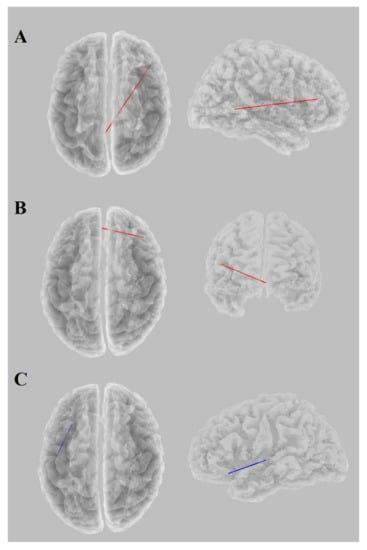

3.2. EEG Analysis